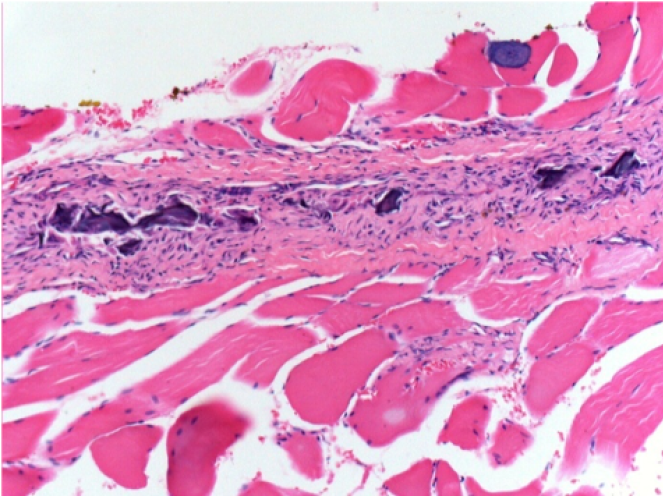

1 mese dopo Iniezione Endopeel

1 mese dopo Iniezione 0.1ml di Endopeel nel muscolo pretibiale destro ( Dx) .

Che cosa viene visualizzato in nero nella figura Sx : 100x-Giorno30 non é una necrosi come potrebbe immaginare un dilettante.

In effetti, 4 conclusioni devono essere prese in considerazione

- un artefatto di colorazione

- un`assenza di necrosi

- un`apoptosi

- un processo biorigenerativo

Sx : Controllo-100x-Giorno30

Dx:100x-Giorno30

Dx :400x-Giorno30